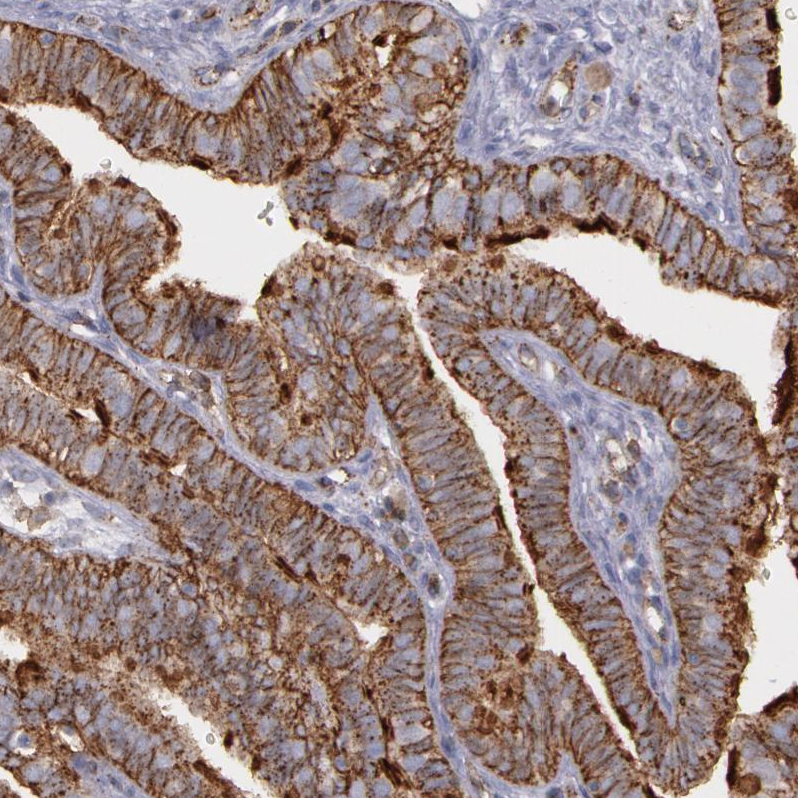

Immunohistochemical staining of human lymph node shows strong membranous positivity in germinal center cells.